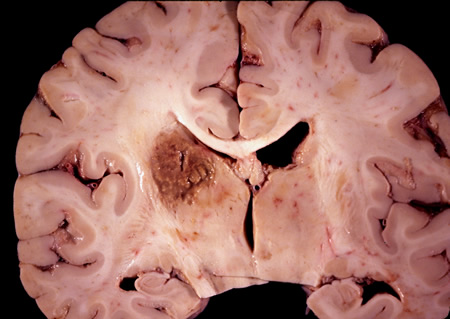

Corte coronal do cérebro de um paciente com vírus da imunodeficiência humana (HIV) com toxoplasmose, exibindo infecção da parte superior periventricular do tálamo esquerdo

Do acervo pessoal de Robert E. Schmidt; usado com permissão